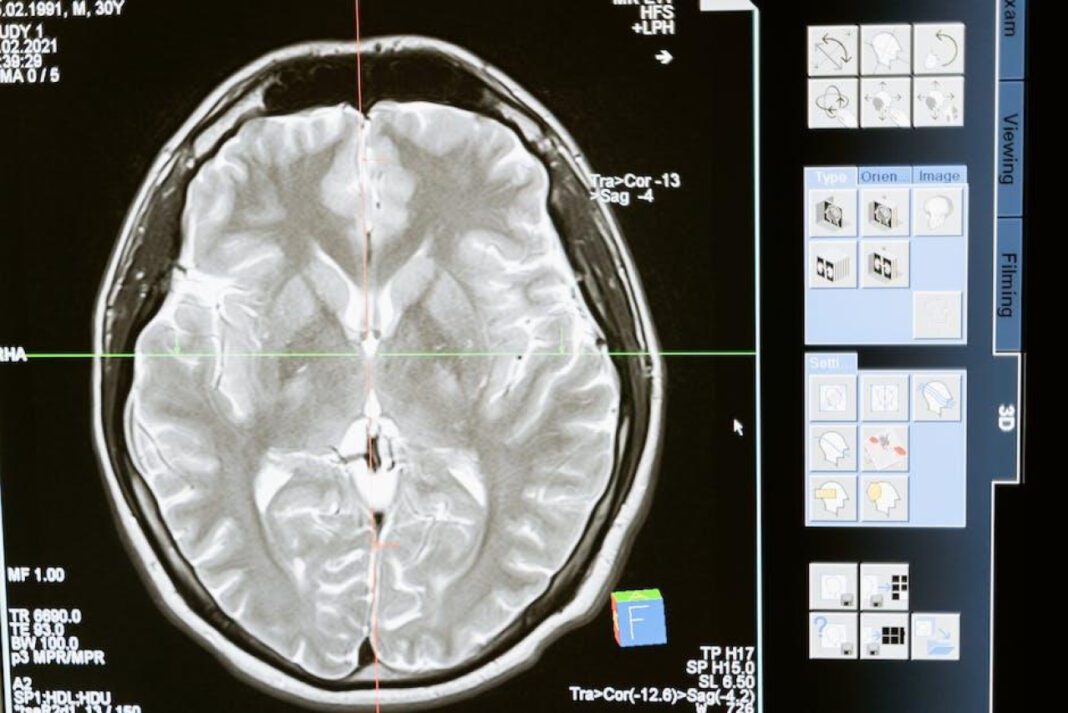

‍ The human brain is an astonishingly complex organ, ⁤responsible ‌for every thought, sensation, and movement. When ⁣doctors need to investigate⁢ the⁢ inner workings of this vital organ,​ they ⁢often turn to‌ magnetic resonance imaging (MRI)​ for a clear and detailed view.⁤ However, the⁢ advanced ⁤technology and expertise involved in conducting a brain MRI come at ‍a cost. In this article, ‍we will explore the various factors that​ contribute to ⁣the price of a brain MRI, ‌from the equipment used to the expertise of​ the radiologists interpreting the results. Whether you’re a patient in need‍ of an⁢ MRI or simply curious about the medical industry, join​ us as we delve into the⁣ financial side of this important ⁢diagnostic tool.

When it comes to medical imaging, ⁤ Brain ​MRI scans are one of the ​most commonly sought after procedures. They provide detailed images of the brain and are crucial in diagnosing and monitoring various‍ neurological⁤ conditions. However, the cost of these scans can vary ⁣widely depending on a number of factors.